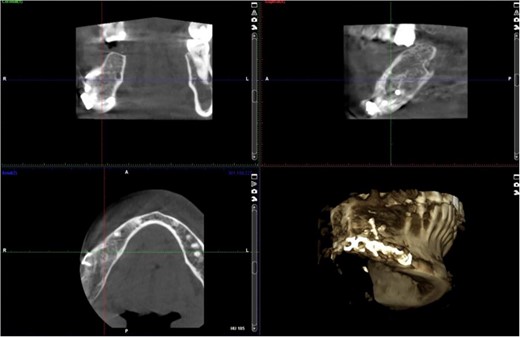

The excised specimen’s histopathology confirmed its benign nature. One year postoperatively, the patient showed no infection or inflammation, with optimal mouth opening and mandibular movement. The reconstruction plate remained stable and intact (Figs 6 and 7).

Postoperative panoramic radiograph demonstrating the reconstruction plate in place after tumor resection and bone grafting.

Follow-up panoramic radiograph showing stable reconstruction plate and no signs of recurrence one year postoperatively.